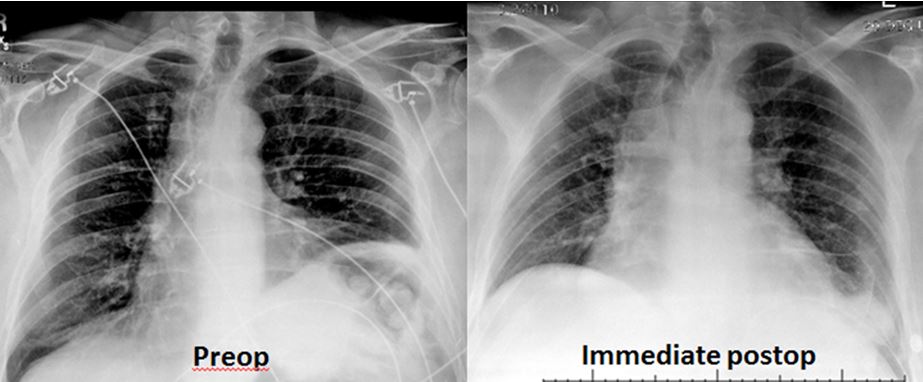

Postoperatively, patients participate in intense pulmonary toilet to re-expand the lower lobe of the ipsilateral lung. The chest drain remains in place until output is less than 200 mL/day. Occasionally patients need to be discharged with the chest tube in place. Premature removal of the chest drain can lead to symptomatic pleural effusion with recurrent lower-lobe atelectasis. The immediate postoperative chest x-ray should show that the plicated side is lower than the opposite side, with an acute costophrenic angle, and that the opposite side is actually elevated in comparison to the preoperative chest x-ray (Figure 5). Patients are monitored with the St. George’s Respiratory Questionnaire (SGRQ), PA/LAT chest x-ray, and PFTs at one month after discharge and yearly thereafter.